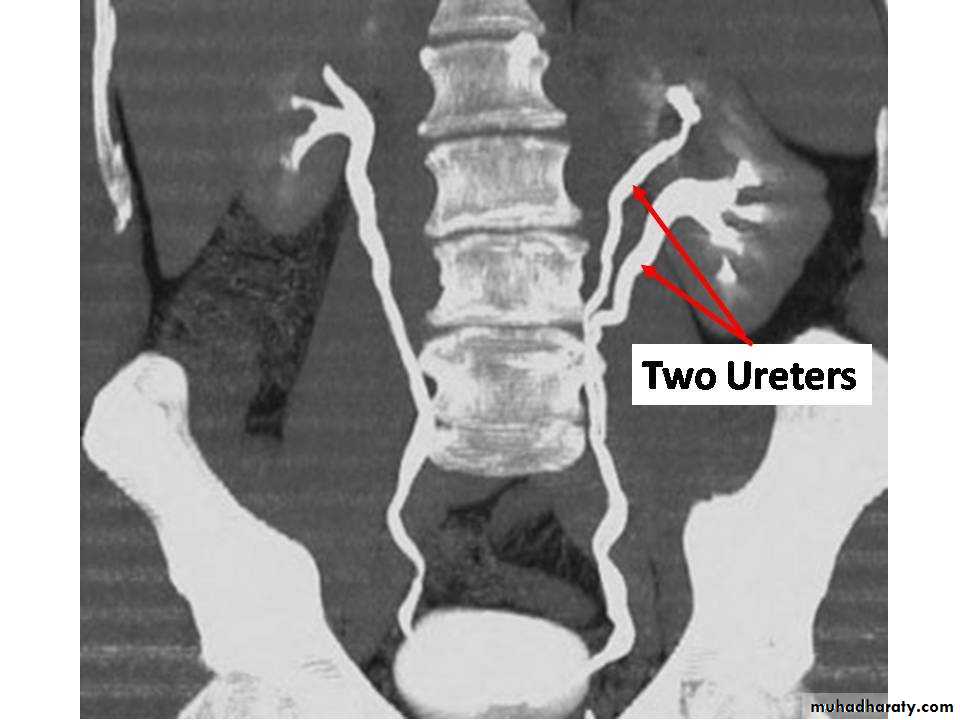

DUPLICATIONS

URETER

Often join together before reaching bladder or may be complete and open independently in the bladder the ureter of upper moiety opens

distal and medial to its fellow and suffer ureterocele or VUR OR ECTOPIC

COMPLICATIONS REPEATED UTI OR STONE FORMATION

TREATMENT

Asymptomatic no treatment if complications treaTment is accordingly